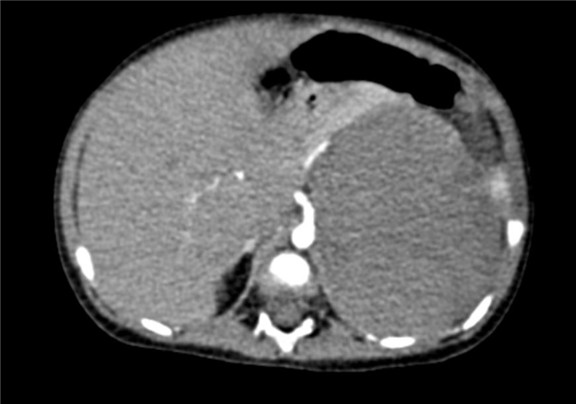

术前CT检查:

动脉期

2017-02-03 上腹部CT平扫:左肾区巨大占位,肾母细胞瘤?建议CT增强检查;右肾结石可能性大;腹腔积液。